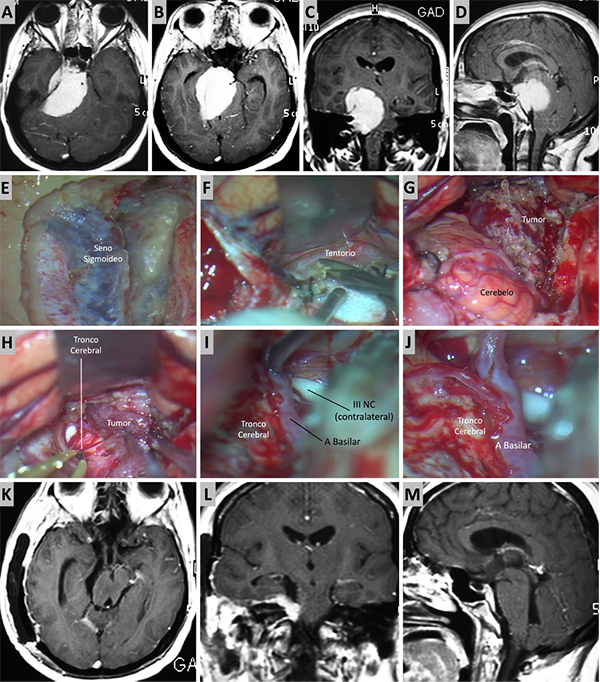

Figura 9. Caso ilustrativo #7. A-B. Meningioma de la MRPC con implantación petrosa anterior. C-F. Se realiza un abordaje subtemporal y petrosectomia anterior. G-H. Imagen por RMN. Resección completa.

Figura 10. Caso ilustrativo #8. MRPC con implantación petroclival con invasión con extensión a la fosa media, clivus inferior, agujero magno y región premedula. Paciente con anacusia izquierda. A. Se observa un corte axial. MPC con extensión al ángulo pontocerebeloso y compromiso del CAI. B. Se observa extensión del tumor a la fosa media, seno cavernoso y ala mayor del esfenoides. C. Se observa extensión del tumor a ala menor del esfenoide, cisterna silviana y optocarotidea.D-E. Extensión del tumor a la fosa media, al clivus inferior y a la región premedular. Se realizo un abordaje presigmoideo acompañado de un abordaje far-lateral y un abordaje retrosigmoideo. F. Se observa la porción tumoral ubicada en el foramen magno y la región premedular, fue necesario un abordaje far-lateral. G. Resección completa de la porción ubicada en foramen magno y región premedular. H. Porción tumoral que se extiende desde clivus inferior a clivus medio. I-J. Resección de tumor de clivus medio e inferior. K. Porción tumoral en clivus superior con extensión a fosa media. Se realizo un abordaje transpetroso anterior para esta región. L-M. Resección casi total. N-R. Imágenes postquirúrgica que muestran una resección casi total.

Figura 11. Caso ilustrativo #9. A-D. Imagen por RMN que muestran MRPC con implantación petroclival, extensión a la fosa craneal media y clinoides anterior. F-L. Se realizo un abordaje combinado con clinoidectomia anterior extradural y petrosectomia anterior. N-Q. Se consiguió una resección casi total. Imágenes postquirúrgica por RMN.